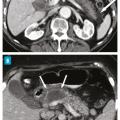

Score modifié de sévérité scanographique

La scanographie (sans et avec injection de produit de contraste) est l’examen de référence dans l’évaluation morphologique de la gravité avec l’évaluation de l’inflammation et de la nécrose de la glande (figure). Elle ne doit être réalisée que soixante-douze heures après le début des symptômes pour ne pas sous-­évaluer les lésions (tableau).5